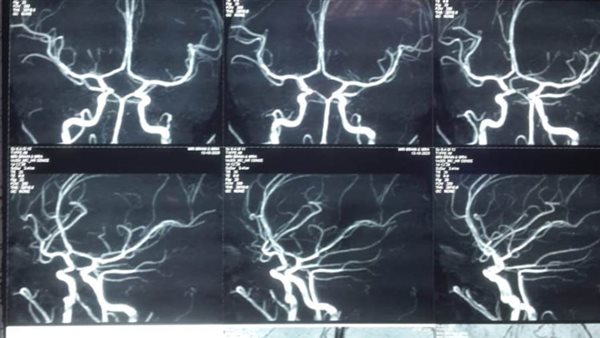

وكان المستشفى استقبل طفلة تبلغ من العمر 11 عاما، تعاني من نزيف ببطينات المخ أدى إلى تدهور شديد فى درجة الوعي لارتفاع ضغط السائل النخاعي على جذع المخ، وتم التدخل الجراحي العاجل من الفريق الطبي، وعمل الجراحة بطريقة بسيطة باستخدام جهاز ( CVP)، وتحويل مسار السائل تحت فروة الرأس ventricluosubgaleal shunting.

واستغرقت العملية حوالي خمس ساعات، وتعد من الجراحات المتقدمة ذات المهارة الخاصة، حيث كان الحل في هذه الحالات هو تركيب صمام مخي بريتوني دائم، وقد يؤدى إلى مضاعفات، أو تركيب صمام لخارج المخ في جهاز تجميع خارجي، وقد يؤدي إلى التهابات بالسحايا المخية.